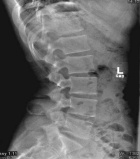

17 year old male with 1.5 year history of low back pain. Activities exacerbate pain.

Zoom image: Radiological image Radiological image.